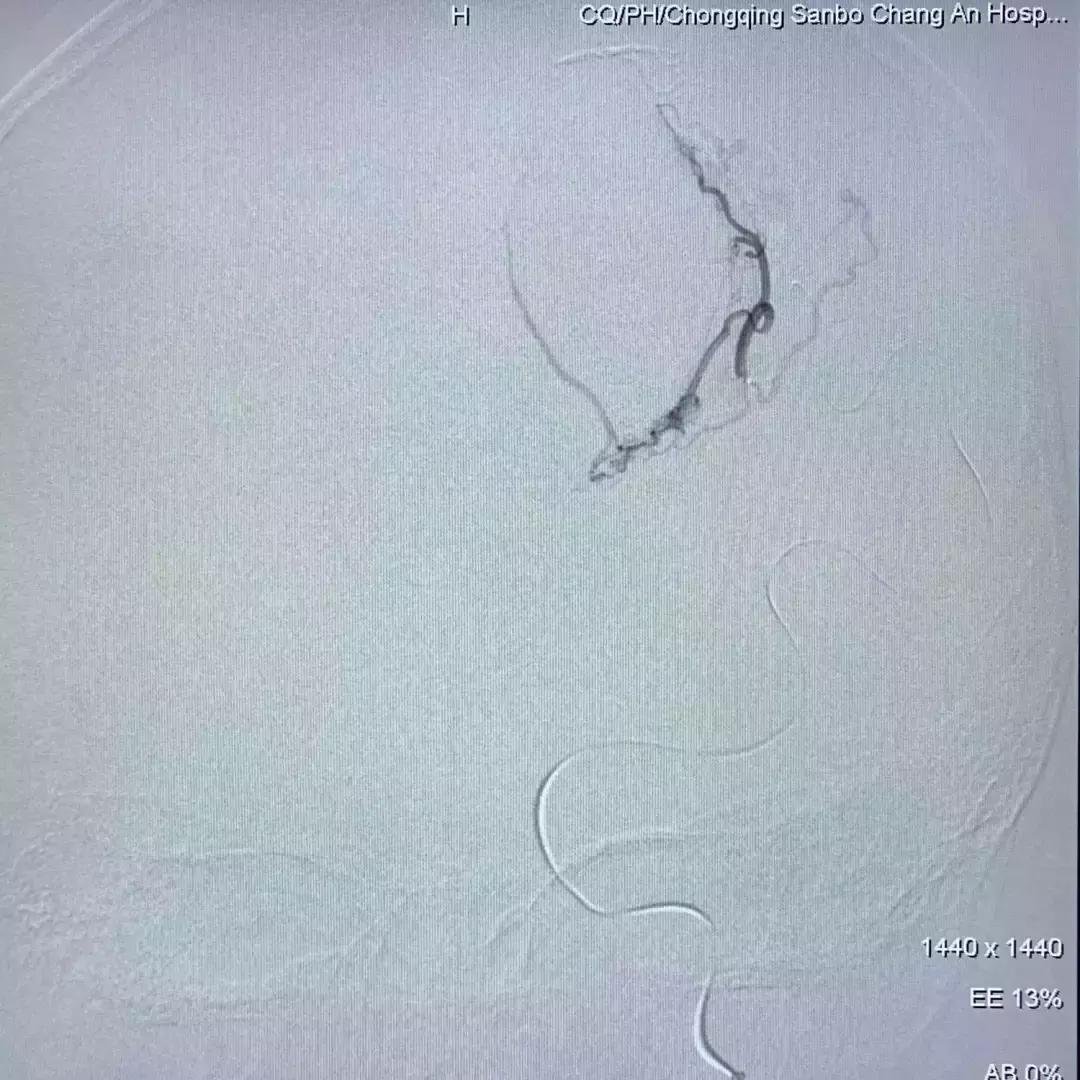

上图为栓塞后的造影